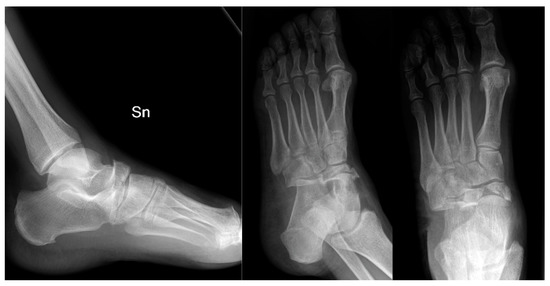

2. Case Presentation